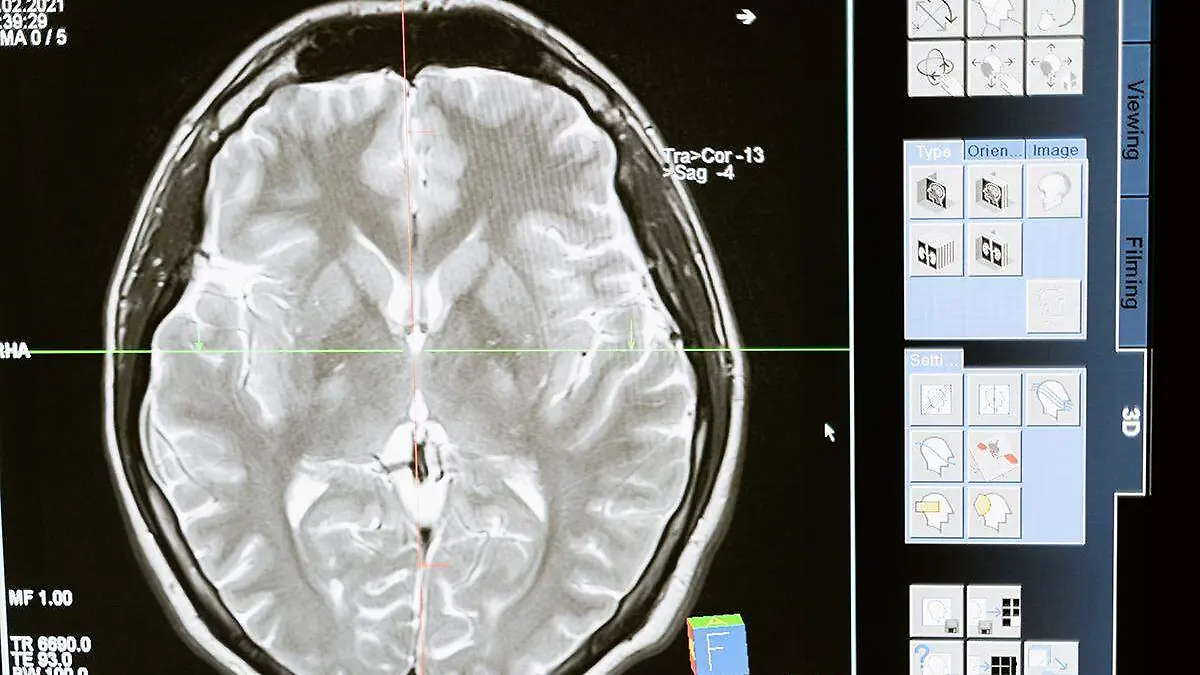

17 de octubre de 2023Instalan en Suecia paradas de autobús para adultos mayores con Alzheimer o demencia